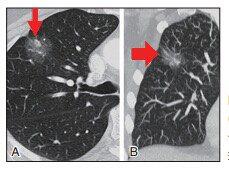

▲图2 患者男性,47岁。良性纯 GGO 结节。A.薄层CT扫描显示右上肺叶一个7 mm的纯结节GGO;B.薄层CT显示病变6个月后不减少或不消失。病理检查示局灶性肺间质纤维化